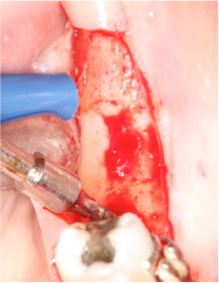

Fig 3, 4 e 5 Observar o posicionamento da broca e o posicionamento do implante com a parte cervical voltada para a lingual e o ápice para vestibular, passando do lado do nervo alveolar.